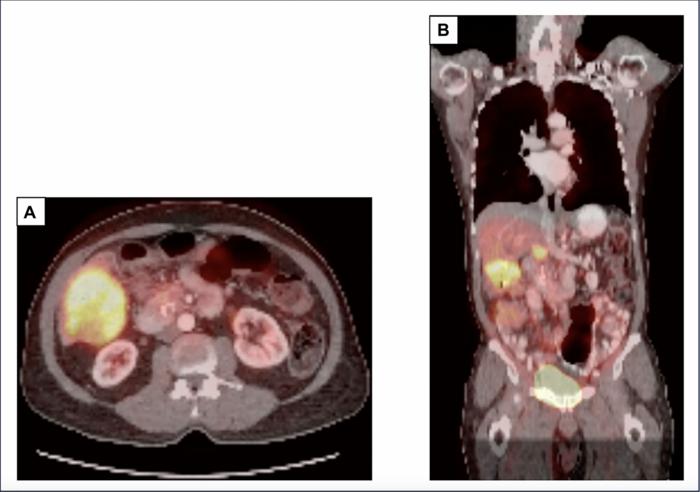

Figure 1: PET-CT scan at our institution prior to staring sotorasib demonstrates an 8.2 cm mass in the right inferior lobe of the liver with a SUV of 10.8 (A, B) and a 2.7 cm pancreatic head mass with a SUV of 5.8 (B). Abbreviations: PET: positron emission tomography; CT: computed tomography.